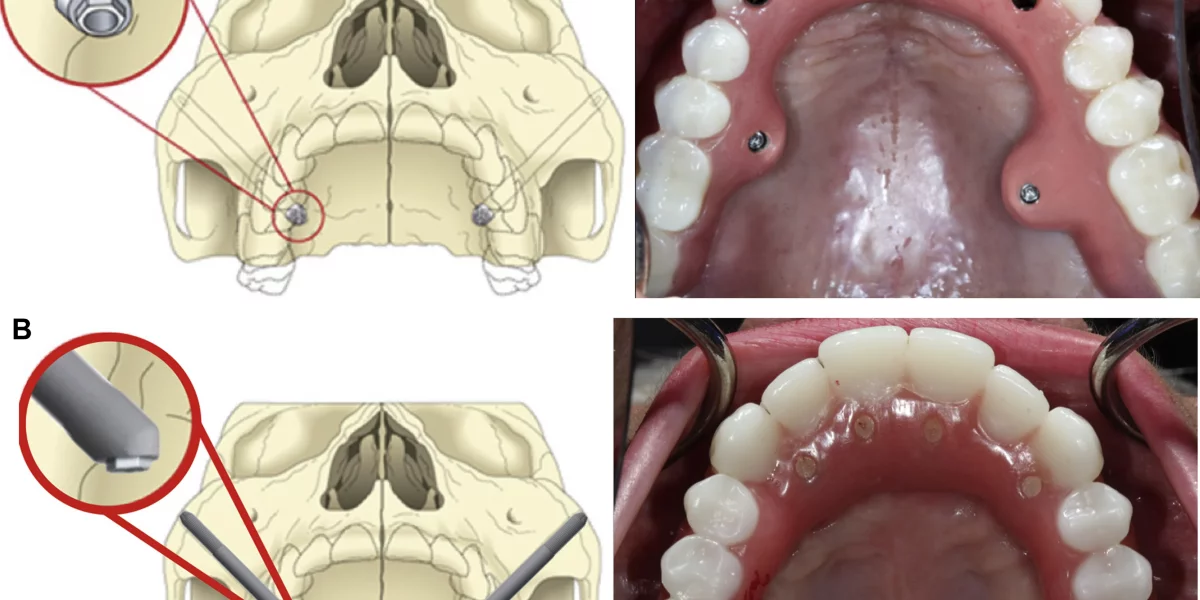

Spre deosebire de implanturile tradiționale care sunt ancorate în osul maxilar superior, implanturile zigomatice sunt mai lungi și plasate în osul zigomatic (osul obrajilor). Această zonă rămâne de obicei densă și sănătoasă chiar și atunci când maxilarul superior a suferit o resorbție extinsă. De aceea, această tehnică este ideală pentru pacienții cu pierderea severă a osului maxilar, care au fost informați că implanturile nu sunt posibile fără grefe de os majore.